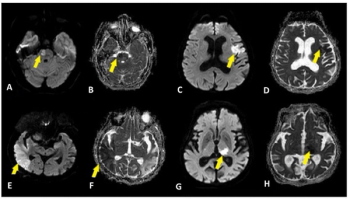

In their review of functional MRI data from over 5,200 study participants, researchers noted that higher amygdala reactivity and lower prefrontal cortical reactivity were associated with adversity exposure, findings that may contribute to exaggerated threat detection and reduced emotional control.